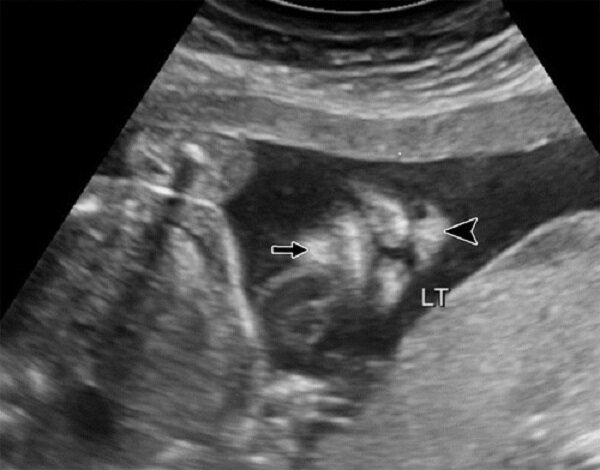

معماران توضیح دادند: جنین از هفته چهارم به اتمام می رسد و لب فوقانی در هفته دوازدهم بارداری شکل می گیرد. بنابراین ، هر عاملی که در این زمان اتفاق می افتد می تواند منجر به عدم وجود لب جنین شود و هرچه زودتر این عوامل اتفاق بیفتد ، شدت شکاف لب و کام بیشتر می شود. وی گفت: غربالگری نقش مهمی در تشخیص این بیماری ایفا می کند ، زیرا لب و کام شکاف ناشی از نقص در رشد بافت صورت در طول جنین است و به جراحی های اصلاحی پیشرفته نیاز دارد.